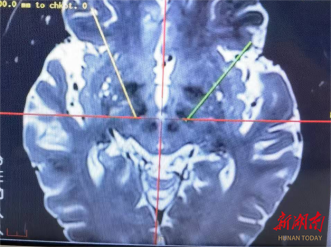

影像学复查提示靶点准确无误,电极无偏移,颅内结构完整无异常。